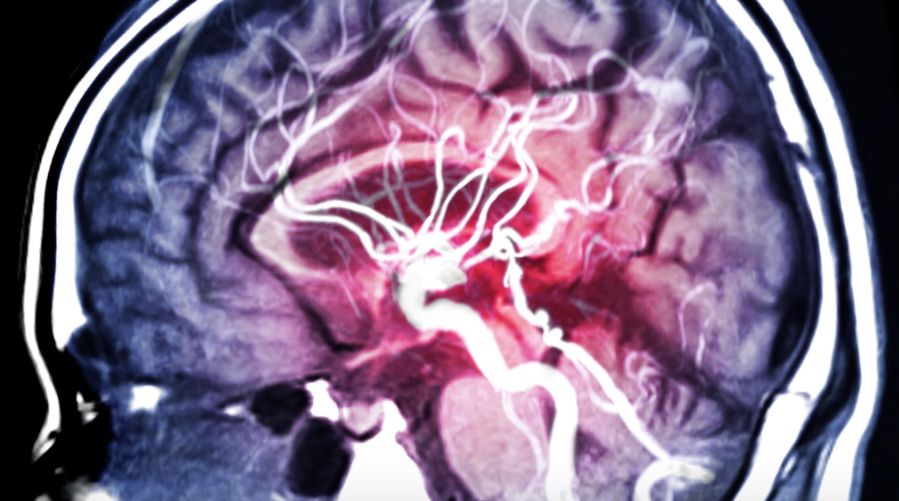

Hirnaneurysma

Ein zerebrales Aneurysma ist eine sackartige Ausstülpung eines Hirngefässes. Eine solche Gefässschwäche kann sowohl angeboren als auch erworben sein. Reisst die dünnhäutige Wand und das Aneurysma platzt, kann es zu einer gefährlichen Blutung in die Hirnwasserräume kommen (Subarachnoidalblutung).  Jährlich erleiden in der Schweiz bis zu 700 Personen eine solche Blutung. Ohne eine Behandlung sterben ca. … Weiterlesen